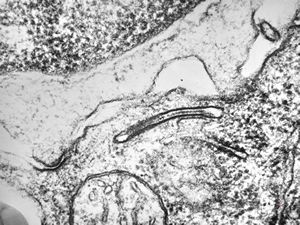

M,51y. | tubular convolution - scrotal sarcoma

F,6y. | tubular convolution, perhaps obliquely sectioned - epithelial tumor of the lip